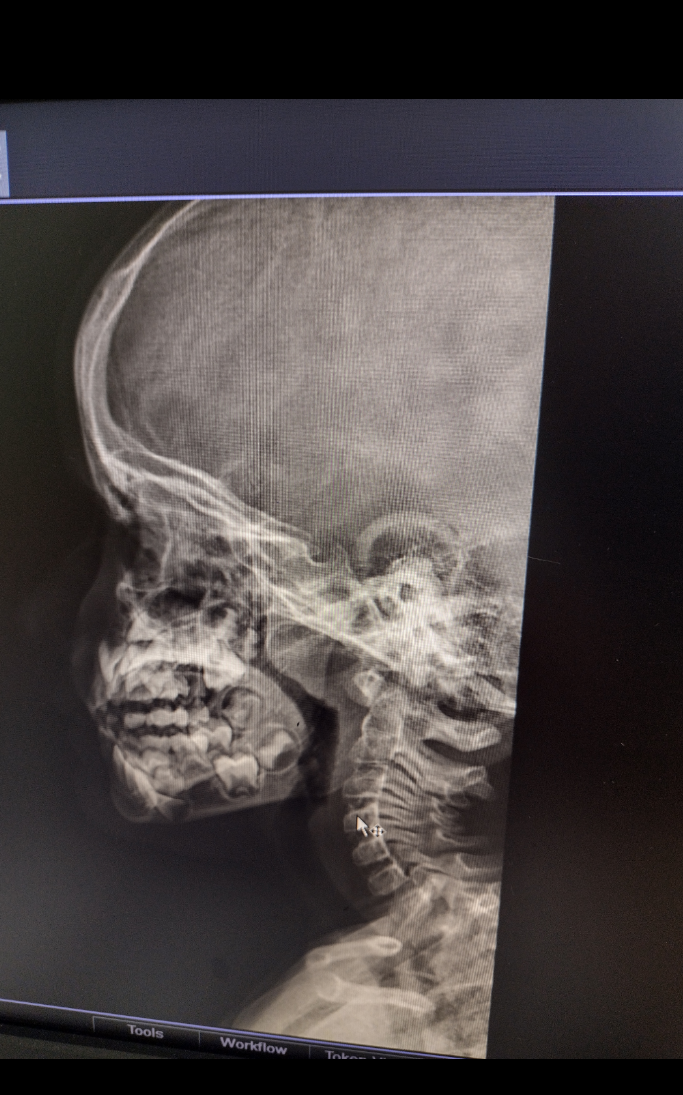

Здравейте! Сина ми е на 3г8м и от почти година, кашля постоянно. Имам съмнение, че изкара коклюш, а педиатъра го лекува, като обикновена кашлица(с няколко различни сиропа). Бяхме на преглед при Аврамова(Студентска поликлиника), която назначи снимка. Вижда се голяма трета сливица и стеснени на 50% дихателни пътища. Тя ми препоръча Станислав Йорданов(Окръжна болница) и Свиден Яначков(СофияМед). Тук четох коментари за Кюлев(Токуда) и Кукушев(ВМА), но освен на едно(за Яначков), не попаднах на мнения за първите двама. За Кюлев има часове, чак за декември. Как запазихте час за Кукушев, през ВМА или в личния му сайт?